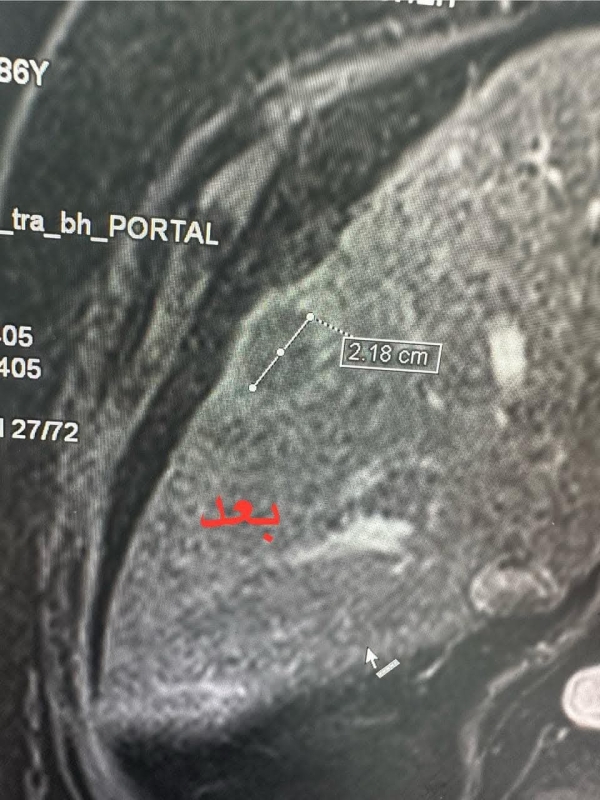

كما بيّنت رئيس قسم الأشعة عقيد طبيب مستشار ديانا الجمال، أن صور المتابعة للمريض بالرنين المغناطيسي للكبد أظهرت كَي الورم كاملاً ، مضيفة أن هذه التقنية تعتبر من التقنيات الحديثة في علاج الأورام التي لا يمكن استئصالها جراحيا.